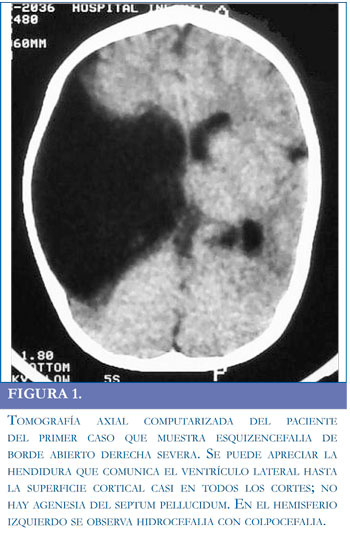

Paciente masculino de 6 años traído a consulta por retardo psicomotor global, con antecedentes de cierre prematuro de fontanelas, perímetro cefálico disminuido y aumento del tono muscular (manos cerradas permanentemente). Estos hallazgos motivaron la realización de una tomografía axial computarizada (TAC) que mostró esquizencefalia de labio abierto derecha (Figura 1). Se evidenció actividad paroxística epileptiforme derecha en un electroencefalograma realizado por presentar el paciente episodios compatibles con espasmo del sollozo.

Con respecto a los potenciales evocados somatosensoriales (Figura 3) es interesante mencionarque en el caso 2 no se encontró respuesta cortical (onda P37) en ninguno de los electrodos explorados (Cz, C3 y C4); por el contrario, en el caso 1 se halló una respuesta normal en el hemisferio cerebral conservado (electrodo C3) y no hubo respuesta en el lado de la lesión (electrodo C4). La ausencia de la respuesta refleja probablemente la ausencia del tejido encefálico encargado del procesamiento cortical del estímulo somatosensorial. Por tanto, los resultados de los potenciales somatosensoriales son coherentes con el cuadro clínico y con las imágenes cerebrales.